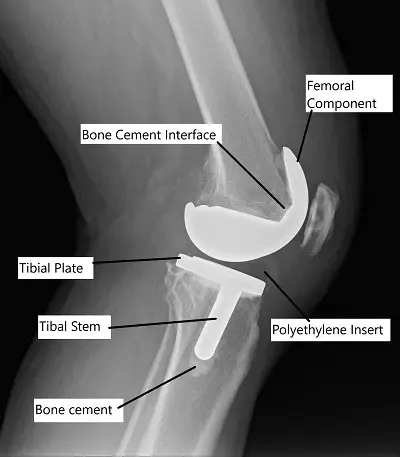

En la prótesis de rodilla, se extraen el cartílago y el hueso desgastados e insertan los implantes protésicos. El método de fijación del implante, ya sea cementado o sin cemento, afecta al rendimiento a largo plazo de la articulación de la rodilla.

Reemplazo total de rodilla cementado

Tras recibir el alta médica para la cirugía y la anestesia adecuada, la articulación de la rodilla se abre por delante. Se extraen los segmentos enfermos de los huesos que forman la articulación. Usando guías de corte, se hacen cortes óseos en el fémur, la tibia y la rótula.

Tras lavar a fondo los segmentos cortados, se aplica cemento óseo acrílico sobre los implantes y los segmentos óseos. Los implantes se fijan entonces en la cama preparada sobre el hueso.

Se fija un espacio de polietileno de alta calidad en plástico al componente tibial para reducir la fricción entre los implantes. El cemento acrílico se endurece rápidamente y proporciona una fijación inmediata.